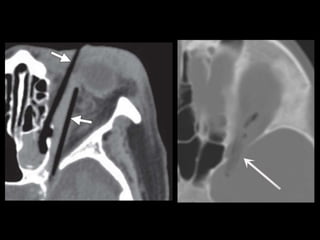

Fracturas simples

• Fx mandíbula

– Anillo

– Localización

– Conminución

– Desplazamiento

– Canal alveolar

Fracturas simples • Fxmandíbula – Anillo – Localización – Conminución – Desplazamiento – Canal alveolar

• #28 the alveolar process (magenta), parasymphyseal region (blue), body (red), angle (green), ramus (yellow), coronoid process (orange), and condyle (purple).